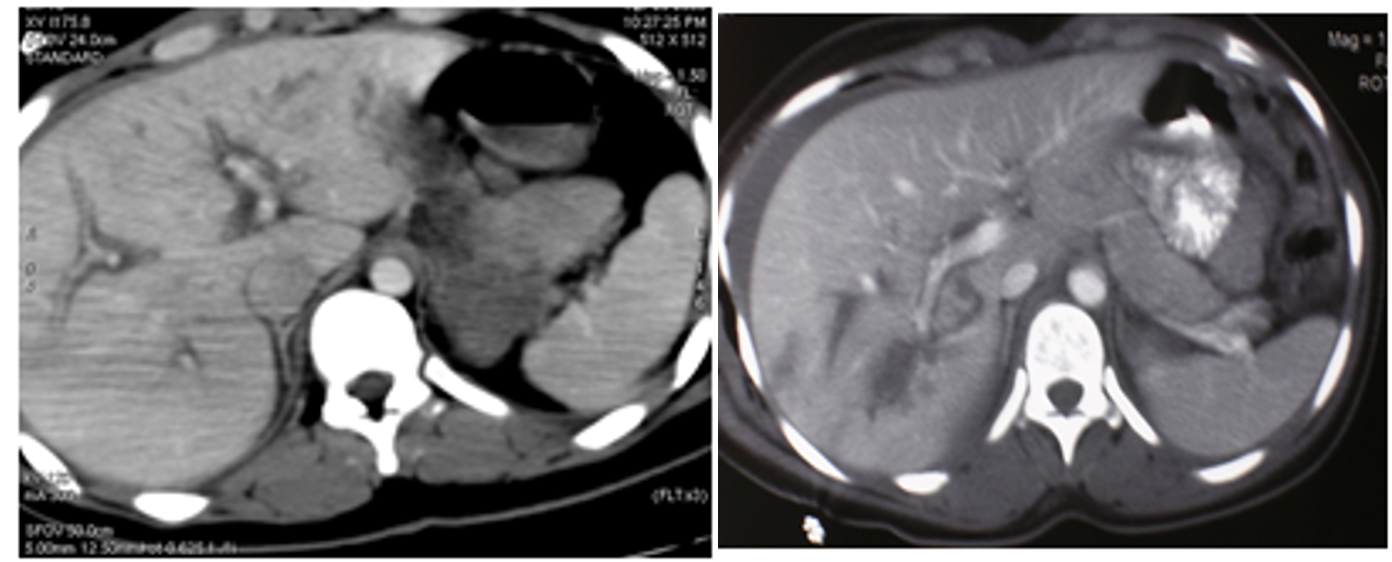

Diagnosis:

- Hemodynamically unstable- FAST

- Hemodynamically stable- FAST, CT scan

- Management based on hemodynamic status

(Image: Liver injury- CT scan)